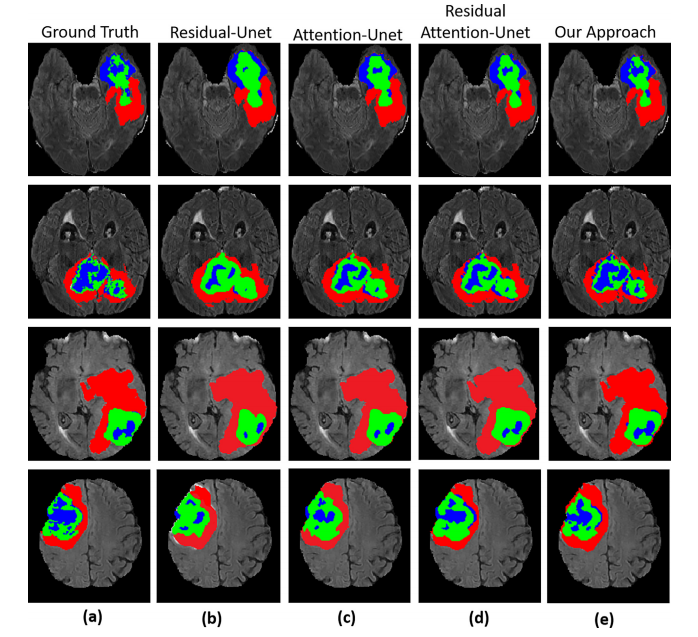

Fig. 7. Segmentation results of the whole tumor, enhancing tumor, and tumor core. (a) represents Ground truth (label), (b) Residual-UNet © AttentionUNet (d) Residual Attention-UNet (e) Our method.

图7. 整个肿瘤、增强肿瘤和肿瘤核心的分割结果。(a) 表示地面真相(标签),(b) 残差UNet,© 注意UNet,(d) 残差注意力UNet,(e) 我们的方法。